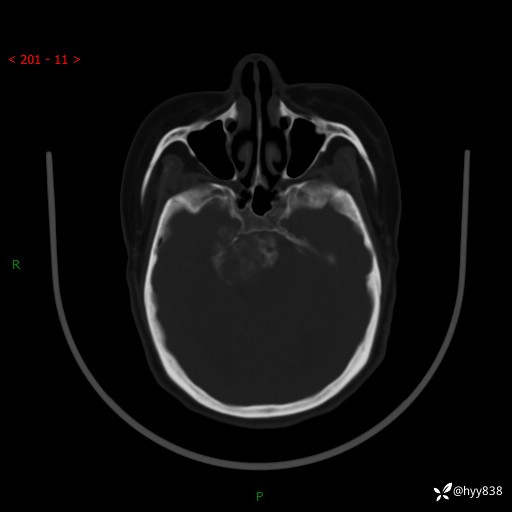

颅脑CT平扫